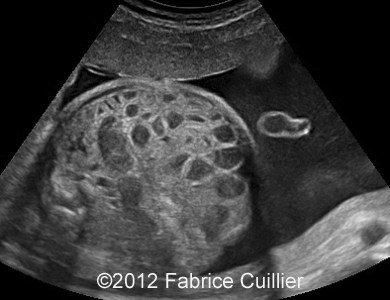

At 32 weeks, the aspect of the intestinal dilatation changed. Low digestive obstruction was suspected (Image 2, 3), with important aggravation at 35 weeks (Image 4). Mesenteric artery and vein had a physiological position (Image 5). Fetal ears and face were normal. Corpus callosus was present (Image 6). The extremities were also normal. Sex was male with bilateral hydrocele (Image 7). Abdominal fetal MRI was performed (Image 8, 9).

Image 2, 3: Slightly intestinal obstruction at 32- 33 weeks.

3A

3B